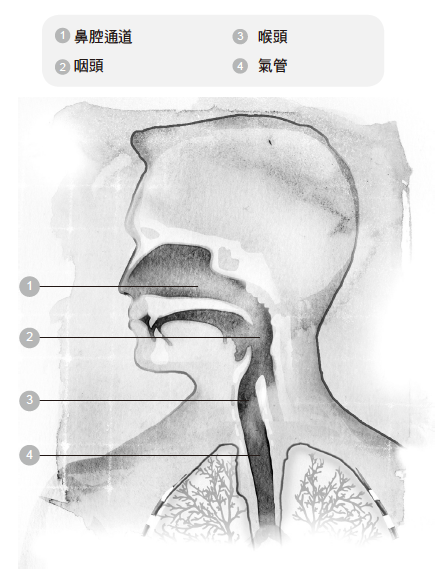

◆鼻子和嘴巴

我们所呼吸的空气是从鼻子和嘴巴进入体内。嘴巴比鼻子更能吸入大量的空气,原因在于嘴巴的空间比鼻腔的通道更大。人们说话、唱歌、吹奏管乐器或是做动作的时候,或许会需要用嘴巴来呼吸。

以嘴呼吸时,空气受到的阻力比较小,因此可以快速进入肺脏。不过,用鼻子呼吸的话,空气是温暖湿润的,而且会受到过滤,对健康有好处。无论以嘴或鼻子呼吸,空气都是经过喉咙的后方,接着再经过气管,继续往下流动。气管进一步分叉成支气管,把空气带进肺脏。

进食的时候,食物和饮料是经过食道而进入胃部,食道位于气管后方。会厌是一小块扁平的软骨,吞咽的时候,会厌会封闭气管,于是食物和饮料被引入胃部,如此便可防止食物经由气管而进入肺脏。

呼吸和吞咽的动作无法同时间进行,这就是为什么当我们吃饭吃得太急,或是一边吃饭一边说话,食物偶尔会跑错了地方。

◆气管

气管是一根大约十公分长的管子,直径不到二.五公分。气管开口位于喉头下方,往下延伸到胸骨的后面。气管是由具有弹性的软骨所构成,不过非常强韧,因为它必须一直保持开放的状态。气管分叉成两根小一点的管子,称为支气管。两边的肺各有一根支气管。

✘误解二:鼻腔里面的通道是朝上的

鼻腔里面的通道到底是什么样的?先来做做下面这个练习,有助于你建立正确的认知。

人们普遍认为空气进入鼻腔的路线是朝上的,事实却不是如此。其实,空气是循着水平的方向前进。现在,试试下面的练习:

觉察练习8

1. 一边想像空气往上进入你的鼻腔,一边呼吸。这个动作说来很简单,实际去做的时候,你有没有觉得必须费力而感到紧绷呢?

2. 这回吸气时,想像空气经由水平路线进入你的鼻腔。有没有觉得轻松许多了呢?这种吸气的方法不会造成任何紧绷感。

翻到下一页的图片,你便会看到,鼻腔的通道大部分是水平的。

察觉练习8的解答

请注意看清楚,空气所走的通道,有一大段是水平的。